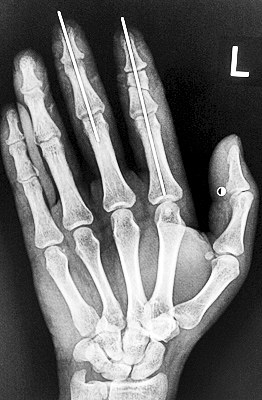

術(shù)后X光顯示,骨骼對位良好。

最終,盧微波和團隊找好了需要的血管和神經(jīng),做好標記后,開始固定食指骨骼、吻合肌腱,最后在顯微鏡下用直徑20微米的無創(chuàng)顯微縫合線開始吻合血管和神經(jīng)。

在經(jīng)過兩個多小時手術(shù)后,早上8時許,盧微波下令松止血帶,數(shù)十秒后男子蒼白的食指逐漸紅潤起來,食指在離體10個小時后恢復(fù)血運。

緊接著,盧微波又開始中指再植手術(shù)。上午10時許,中指在離體12小時后也成功恢復(fù)血運。